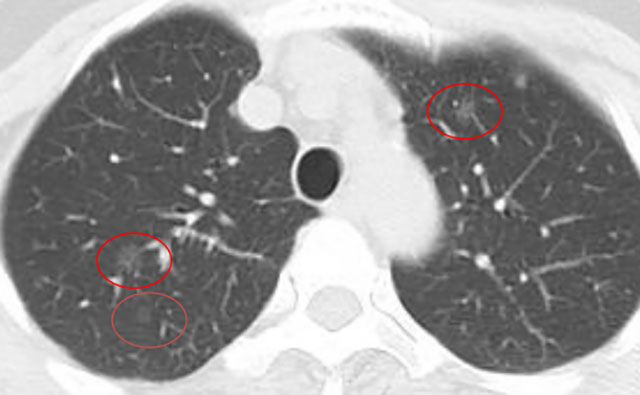

近期,阿姨复查影像展示与分析,1mm层薄层。

与术前及每年复查片对比,阿姨双肺多发磨玻璃结节,均未见显著改变,左肺上叶前段主病灶亦如此,密度很纯,未见增大及实性成分出现,术后5年虽可见血管弯曲,进展极慢,风险还是相对较低,且右肺上叶已经全切除。双肺多发相对较小磨玻璃密度结节,并且进展极慢、仍纯磨密度。该病灶目前没有必须到手术干预程度,只需6-12月复查随访,若有进展并要有风险增加时再考虑干预处理。